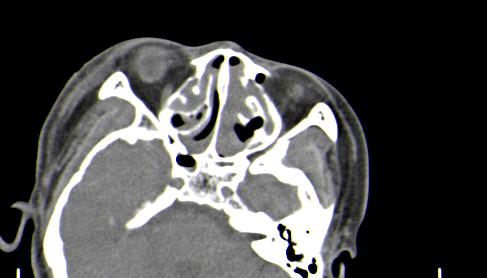

以下是引用皎皎白驹在2006-11-29 8:48:00的发言:[br]影像表现:双侧筛窦和上颌窦、鼻腔内均密度增高,右侧视神经增粗、弯曲,左筛窦顶部筛板及右侧纸板近视神经孔区可见骨折线。[br]结合临床表现考虑:右侧筛窦纸板近视神经孔区骨折致右侧视神经损伤。最好做个眼眶冠状扫描,更明确右侧视神经管是否狭窄。

以下是引用w_jianhua在2006-11-29 10:07:00的发言:[br]影像表现:双侧筛窦和上颌窦、鼻腔内均密度增高,右侧视神经增粗、弯曲,左筛窦顶部筛板及右侧纸板近视神经孔区可见骨折线。[br]结合临床表现考虑:右侧筛窦纸板近视神经孔区骨折致右侧视神经损伤。最好做个眼眶冠状扫描,更明确右侧视神经管是否狭窄。 [br] [br]支持[br]

以下是引用守望可可西里在2006-11-29 9:46:00的发言:[br][quote]以下是引用皎皎白驹在2006-11-29 8:48:00的发言:[br]影像表现:双侧筛窦和上颌窦、鼻腔内均密度增高,右侧视神经增粗、弯曲,左筛窦顶部筛板及右侧纸板近视神经孔区可见骨折线。[br]结合临床表现考虑:右侧筛窦纸板近视神经孔区骨折致右侧视神经损伤。最好做个眼眶冠状扫描,更明确右侧视神经管是否狭窄。